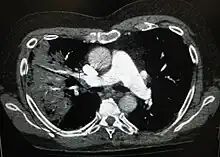

A chest radiograph is frequently used in diagnosis.[23] In people with mild disease, imaging is needed only in those with potential complications, those not having improved with treatment, or those in which the cause is uncertain.[23][67] If a person is sufficiently sick to require hospitalization, a chest radiograph is recommended.[67] Findings do not always match the severity of disease and do not reliably separate between bacterial and viral infection.[23]

X-ray presentations of pneumonia may be classified as lobar pneumonia, bronchopneumonia, lobular pneumonia, and interstitial pneumonia.[73] Bacterial, community-acquired pneumonia classically show lung consolidation of one lung segmental lobe, which is known as lobar pneumonia.[41] However, findings may vary, and other patterns are common in other types of pneumonia.[41] Aspiration pneumonia may present with bilateral opacities primarily in the bases of the lungs and on the right side.[41] Radiographs of viral pneumonia may appear normal, appear hyper-inflated, have bilateral patchy areas, or present similar to bacterial pneumonia with lobar consolidation.[41] Radiologic findings may not be present in the early stages of the disease, especially in the presence of dehydration, or may be difficult to interpret in the obese or those with a history of lung disease.[24] Complications such as pleural effusion may also be found on chest radiographs. Laterolateral chest radiographs can increase the diagnostic accuracy of lung consolidation and pleural effusion.[40]

A CT scan can give additional information in indeterminate cases[41] and provide more details in those with an unclear chest radiograph (for example occult pneumonia in chronic obstructive pulmonary disease). They can be used to exclude pulmonary embolism and fungal pneumonia, and detect lung abscesses in those who are not responding to treatments.[40] However, CT scans are more expensive, have a higher dose of radiation, and cannot be done at bedside.[40]